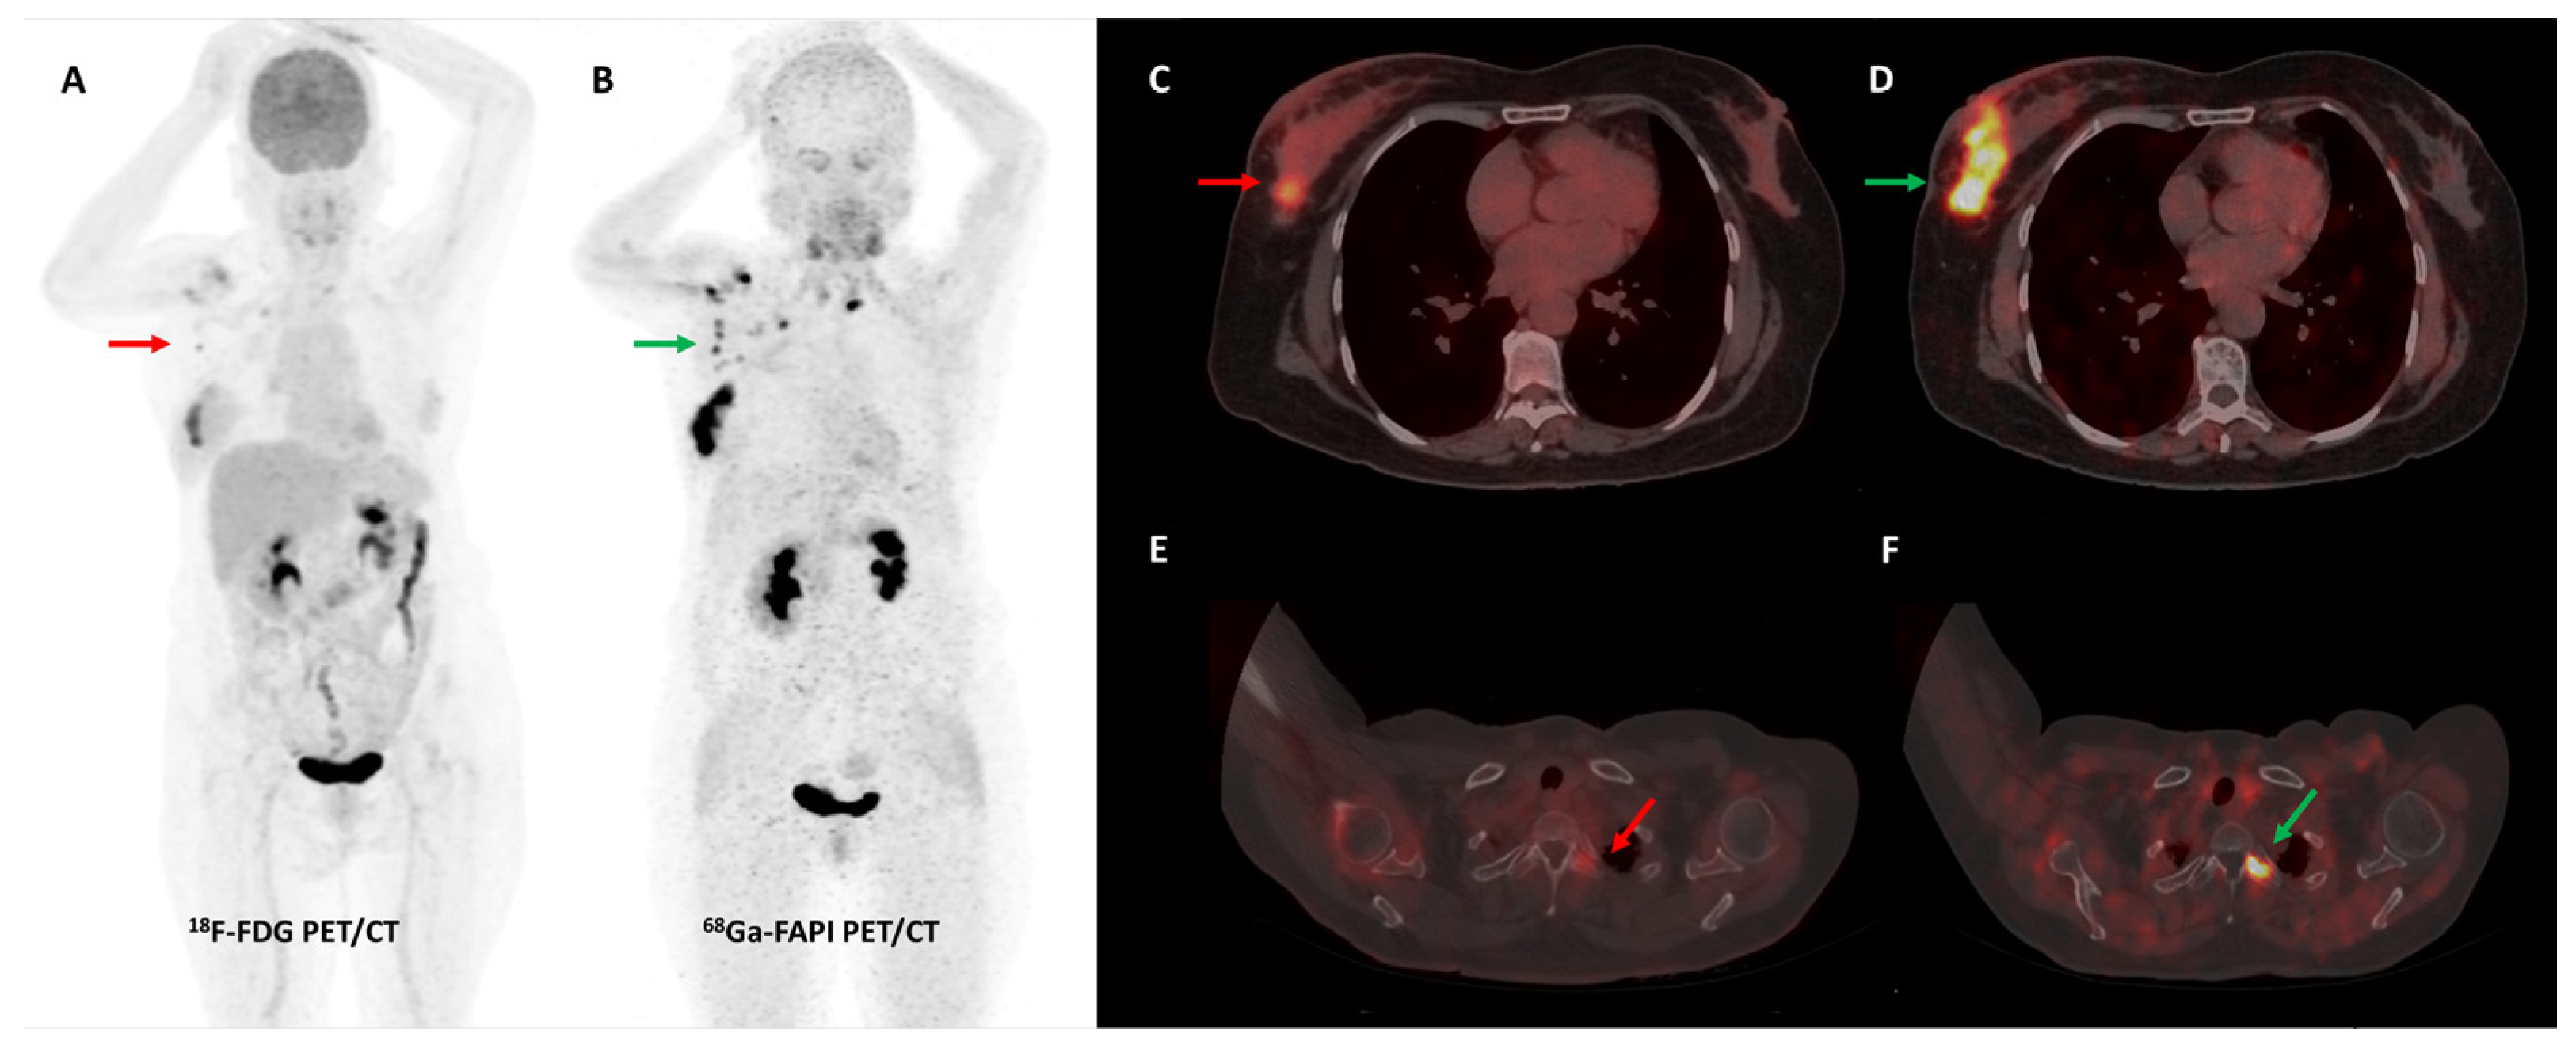

- Kömek, H.; Can, C.; Güzel, Y.; Oruç, Z.; Gündoğan, C.; Yildirim, Ö.A.; Kaplan, İ.; Erdur, E.; Yıldırım, M.S.; Çakabay, B. 68Ga-FAPI-04 PET/CT, a New Step in Breast Cancer Imaging: A Comparative Pilot Study with the 18F-FDG PET/CT. Ann. Nucl. Med. 2021, 35, 744–752. [Google Scholar] [CrossRef] [PubMed]

- Elboga, U.; Sahin, E.; Kus, T.; Cayirli, Y.B.; Aktas, G.; Uzun, E.; Cinkir, H.Y.; Teker, F.; Sever, O.N.; Aytekin, A.; et al. Superiority of 68Ga-FAPI PET/CT Scan in Detecting Additional Lesions Compared to 18FDG PET/CT Scan in Breast Cancer. Ann. Nucl. Med. 2021, 35, 1321–1331. [Google Scholar] [CrossRef]